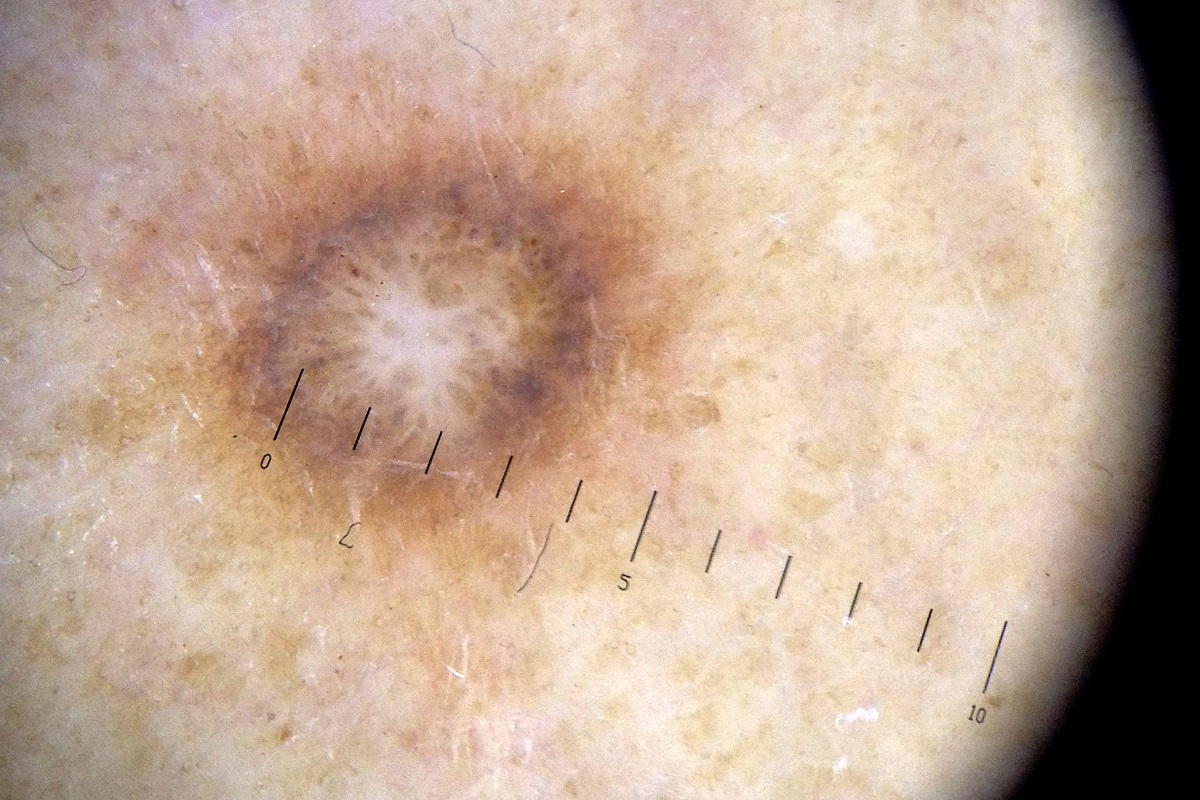

Modermaerke_1200

Jacob Ehrbahn / Ritzau Scanpix

Som en af de første i landet screener den danske it-virksomhed NetIP sine ansatte og deres pårørende for hud- og modermærkekræft. 5 ud af 200 fik konstateret kræft eller tegn på sygdommen. Virksomhedens initiativ er en god ide, mener Kræftens Bekæmpelse.